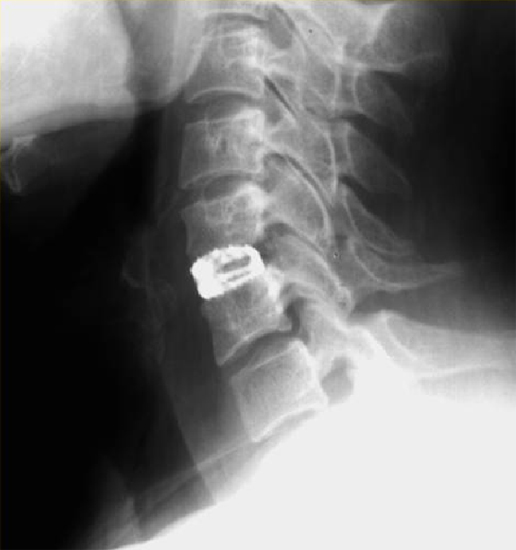

Лечение шейного стеноза хирургическим методом заключается в выполнении декомпрессии позвоночного канала и спинного мозга (т.е. освобождении его от сдавления(компрессии)). В большинстве случаев операция заключается в удалении мп грыжи диска и установке в межтеловое пространство (между двумя смежными телами позвонков) кейджа. (Рис. 4). В настоящее время наиболее современным заменителем диска является искусственный диск. Наиболее близким по строению и функции к обычному диску является искусственный диск «М6-С». (Рис.5) Так же как и настоящий диск указанный имплант состоит 2-х частей: искусственного ядра, обеспечивающего осевое сжатие, и кольца из волокнистого материала, обеспечивающего подвижность с контролируемой амплитудой и с шестью степенями свободы. (Рис.6) Такая конструкция обеспечивает физиологическую подвижность позвоночно-двигательного сегмента и, возможно, предотвращение и отсрочку дальнейшей дегенерации дисков на уровне соседних позвонков. Биомеханические испытания искусственного диска М6-С подтвердили качество подвижности, эквивалентное человеческому диску.

Рис. 4. Рентгенограмма шейного отдела позвоночника в боковой проекции. Имплантированный в межтеловое пространство С5-С6 кейдж, заполненный костной крошкой.